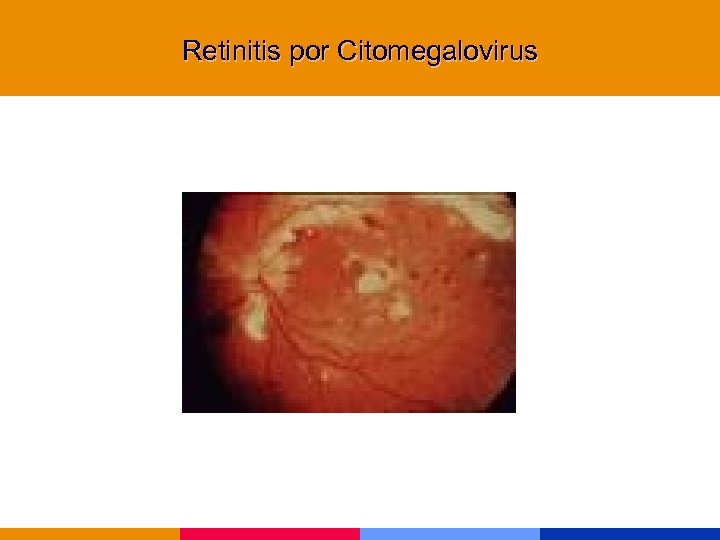

Infecciones por CMV § Afectan a pacientes severamente inmunocomprometidos § Afección de la retina, tubo digestivo, SNC y pulmón § Diagnóstico de retinitis: oftalmólogo entrenado

Infecciones por CMV § Afectan a pacientes severamente inmunocomprometidos § Afección de la retina, tubo digestivo, SNC y pulmón § Diagnóstico de retinitis: oftalmólogo entrenado

Retinitis por Citomegalovirus

Retinitis por Citomegalovirus

Retinitis por Citomegalovirus

Retinitis por Citomegalovirus

Retinitis por Citomegalovirus

Retinitis por Citomegalovirus

Retinitis por Citomegalovirus

Retinitis por Citomegalovirus